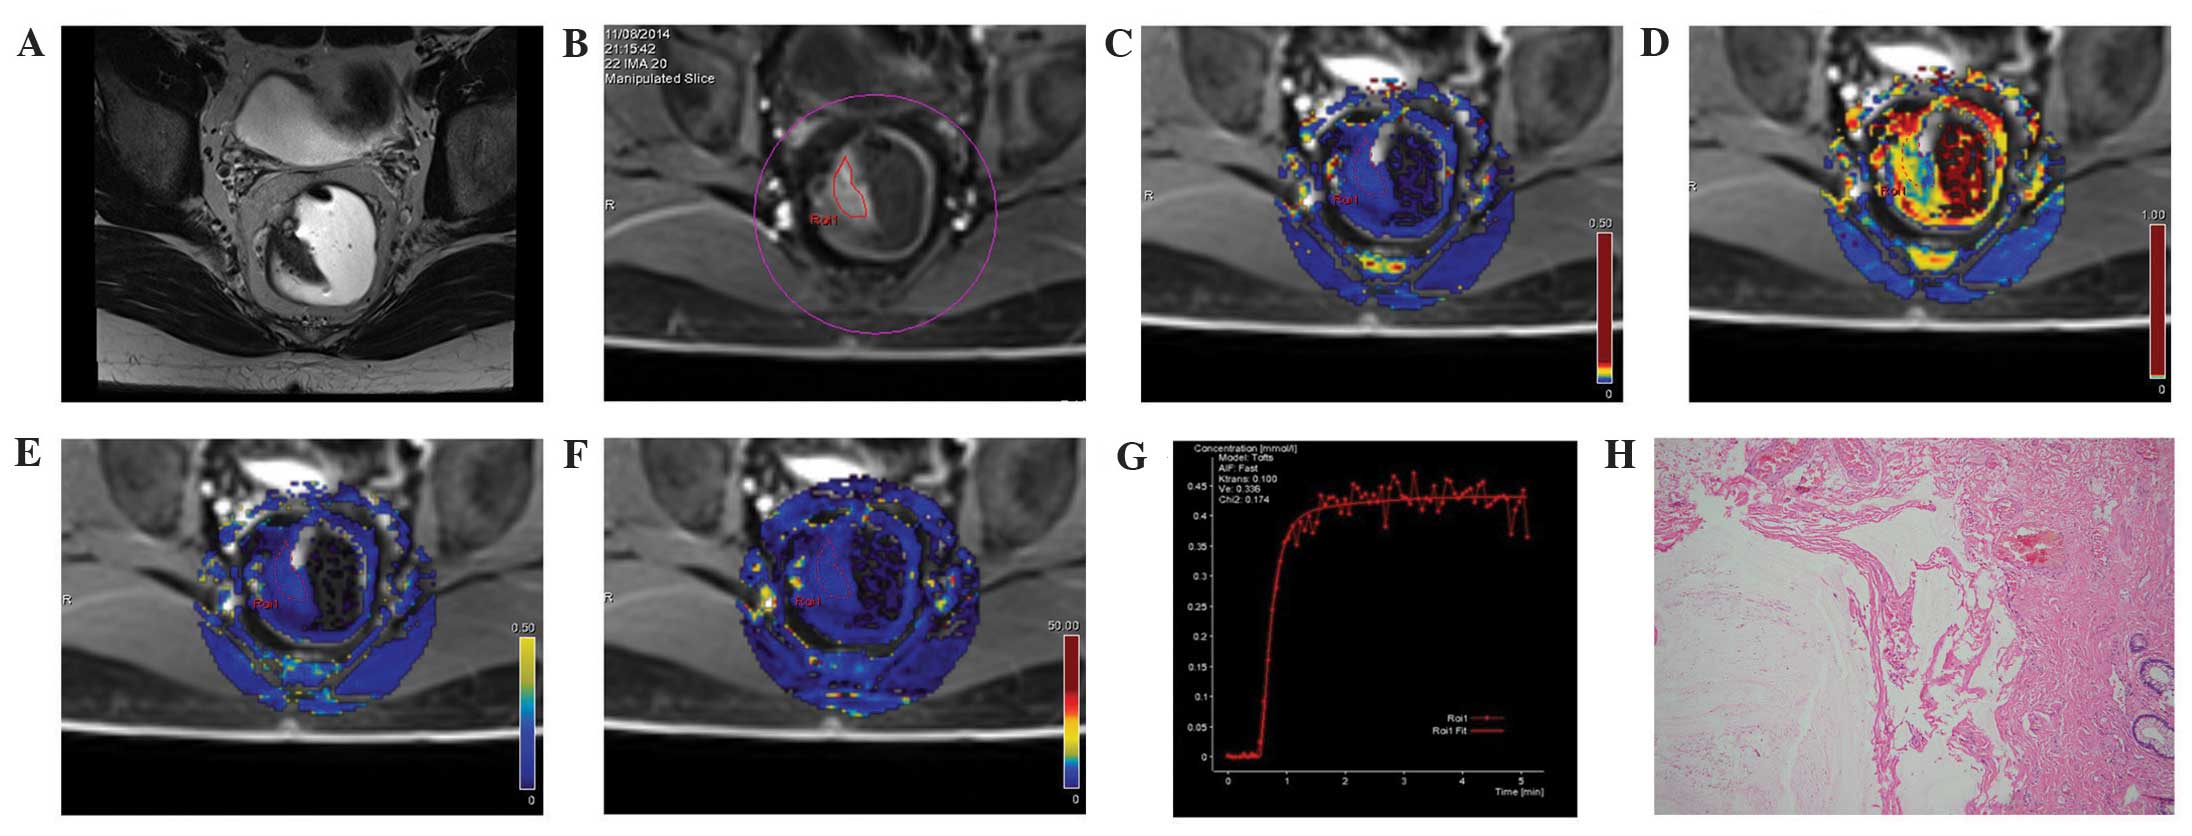

All 40 cases of rectal cancer had a single lesion, of which 26 cases exhibited space-occupying masses, 10 revealing an irregular thickening of the local intestinal wall, and four cases showing abnormal local nodular signals. All lesions demonstrated equal or lower T1WI signals, equal or higher T2WI signals, equal or higher fat-suppression sequence signals, and high DWI signals. Significantly enhanced lesions were capable of being viewed on DCE-MRI. The Ktrans, Kep, Ve, and iAUC values in rectal cancer lesions were all significantly higher compared with the controls (all P<0.05) (Table I). The pseudo-color images of each parameter are shown in Figs. 1 and 2. The time-signal intensity curves showed an outflow pattern: The signal peaked shortly following the injection of the contrast agent, and subsequently quickly decayed by >10% compared with the signal intensity in the mid- and late-stage of the enhancement after the contrast agent was injected (Fig. 1G). On the other hand, in the controls, the time-signal intensity curves revealed a comparatively smaller elevation of signal intensity at the early stage, and a plateau at the later stage (Fig. 2G).

Figure 1.

MRI images from the same patient with rectal cancer, a female aged 48 years with blood in the stool for 6 months. (A) A T2WI cross section, revealing the local occupation of the rear intestinal wall. (B) DCE-MRI scanning image showing a marked enhancement of the rear intestinal wall, which was slightly higher than the surrounding regions. (C) DCE-MRI pseudo-color images of Ktrans. The yellowish-green area indicates the local occupation of the intestinal wall. Ktrans of the lesion area was 0.208, which was higher compared with the surrounding intestinal wall tissue (blue). (D) DCE-MRI pseudo-color images of Kep. The red and yellow areas indicate the lesion area, where Kep was 0.588. (E) DCE-MRI pseudo-color images of Ve. The yellowish-green area indicates the lesion area, where Ve was 0.370. (F) DCE-MRI pseudo-color images of iAUC. The red and yellow areas indicate the lesion area, where iAUC was 37.009, which was higher compared with the surrounding intestinal wall tissue (blue). (G) The DCE-MRI time-signal intensity curve of the patient, where the dashed line indicates the connection between data points and the solid line indicates the fitted curve, reveals an outflow pattern. (H) Results of the postoperative pathology test (hematoxylin and eosin staining, ×200). The tumor tissue showed a papillary and mesh-like alignment. Tumor cells were cubic and of a column-like shape, with big, atypical and deeply stained nuclei, which infiltrated into the superficial muscle layer of the intestinal wall. The patient was diagnosed with moderately differentiated rectal adenocarcinoma. DCE-MRI, dynamic contrast-enhanced magnetic resonance imaging; Ktrans, volume transfer constant from the plasma compartment to the extravascular extracellular space; Kep, rate constant for transfer between extravascular extracellular space and the blood compartment; Ve, volume of extravascular extracellular space per unit volume of tissue; iAUC, initial area under enhancement curve.